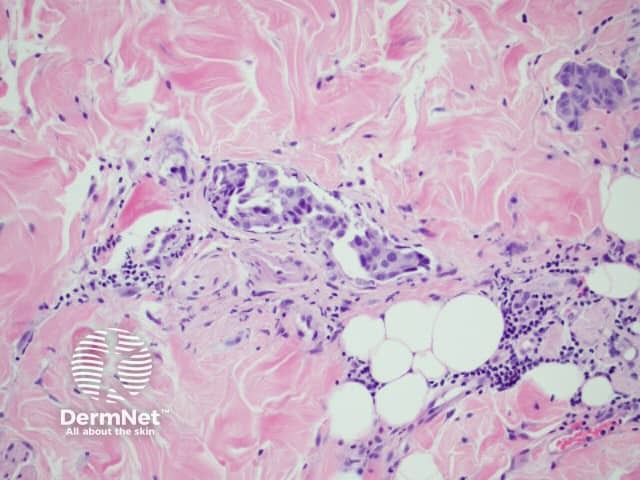

Histological findings of inflammatory carcinoma is distinctive with the deposition of tightly packed malignant cells within the superficial and deep lymphatics without the pathologic evidence of acute inflammation, such as neutrophils, although the lesions look clinically red and inflamed. Dermal lymphatic invasion is considered to be the hallmark of CE. 8

Figure 2